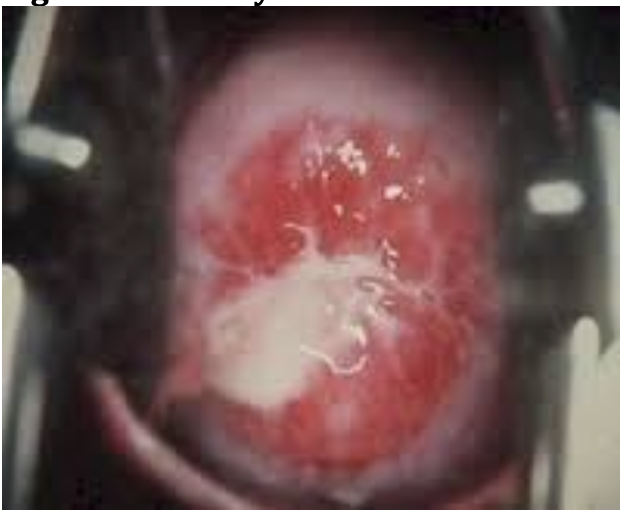

Qu’est-ce?

VPH - verrues génitales